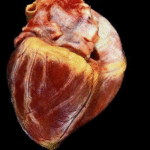

Per praticità, di seguito è possibile confrontare l’aspetto di un “Cuore Normale” e quello di un “Cuore dopo assunzione di Stupefacenti”: la differenza è macroscopica e palese, il cuore subisce una trasformazione delle sue fibre contrattili che si atrofizzano e induriscono, risultando meno efficaci e meno elastiche, rendendo il muscolo cardiaco asfittico e ancora meno efficiente a pompare tutto il sangue necessario, fino allo sfiancamento, tecnicamente la cardiomiopatia dilatativa.

La morte per cardiomiopatia dilatativa avviene a seguito di aritmie ventricolari mortali, edema polmonare acuto, con arresto cardiaco o respiratorio, e questa è probabilmente ciò che è successo alla Pop Star.